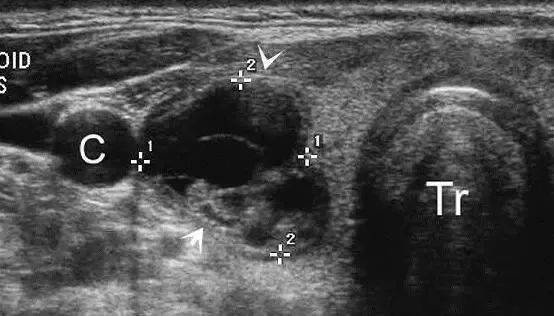

左图:乳头状癌患者,中间两个箭头所指处癌灶已突破甲状腺被膜侵犯颈前肌,外侧两个箭头指向正常甲状腺被膜,其间的正常高回声带(甲状腺被膜)中断。

右图:腺瘤(MASS)虽然很大,但其包膜(指向上方的箭头)与甲状腺被膜(指向下方的箭头)清晰可见,甲状腺被膜无明显中断,反映肿瘤没有侵犯甲状腺被膜。